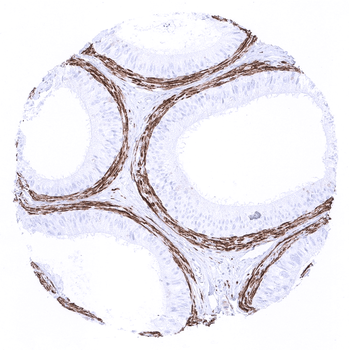

A strong calponin 1 immunostaining occurs in the periductal smooth muscle layer in the epididymis.